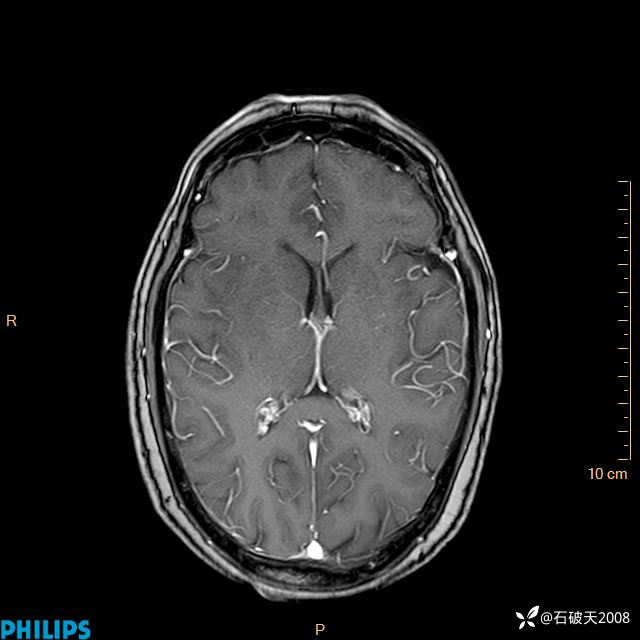

2024.2.21MR

增强轴位